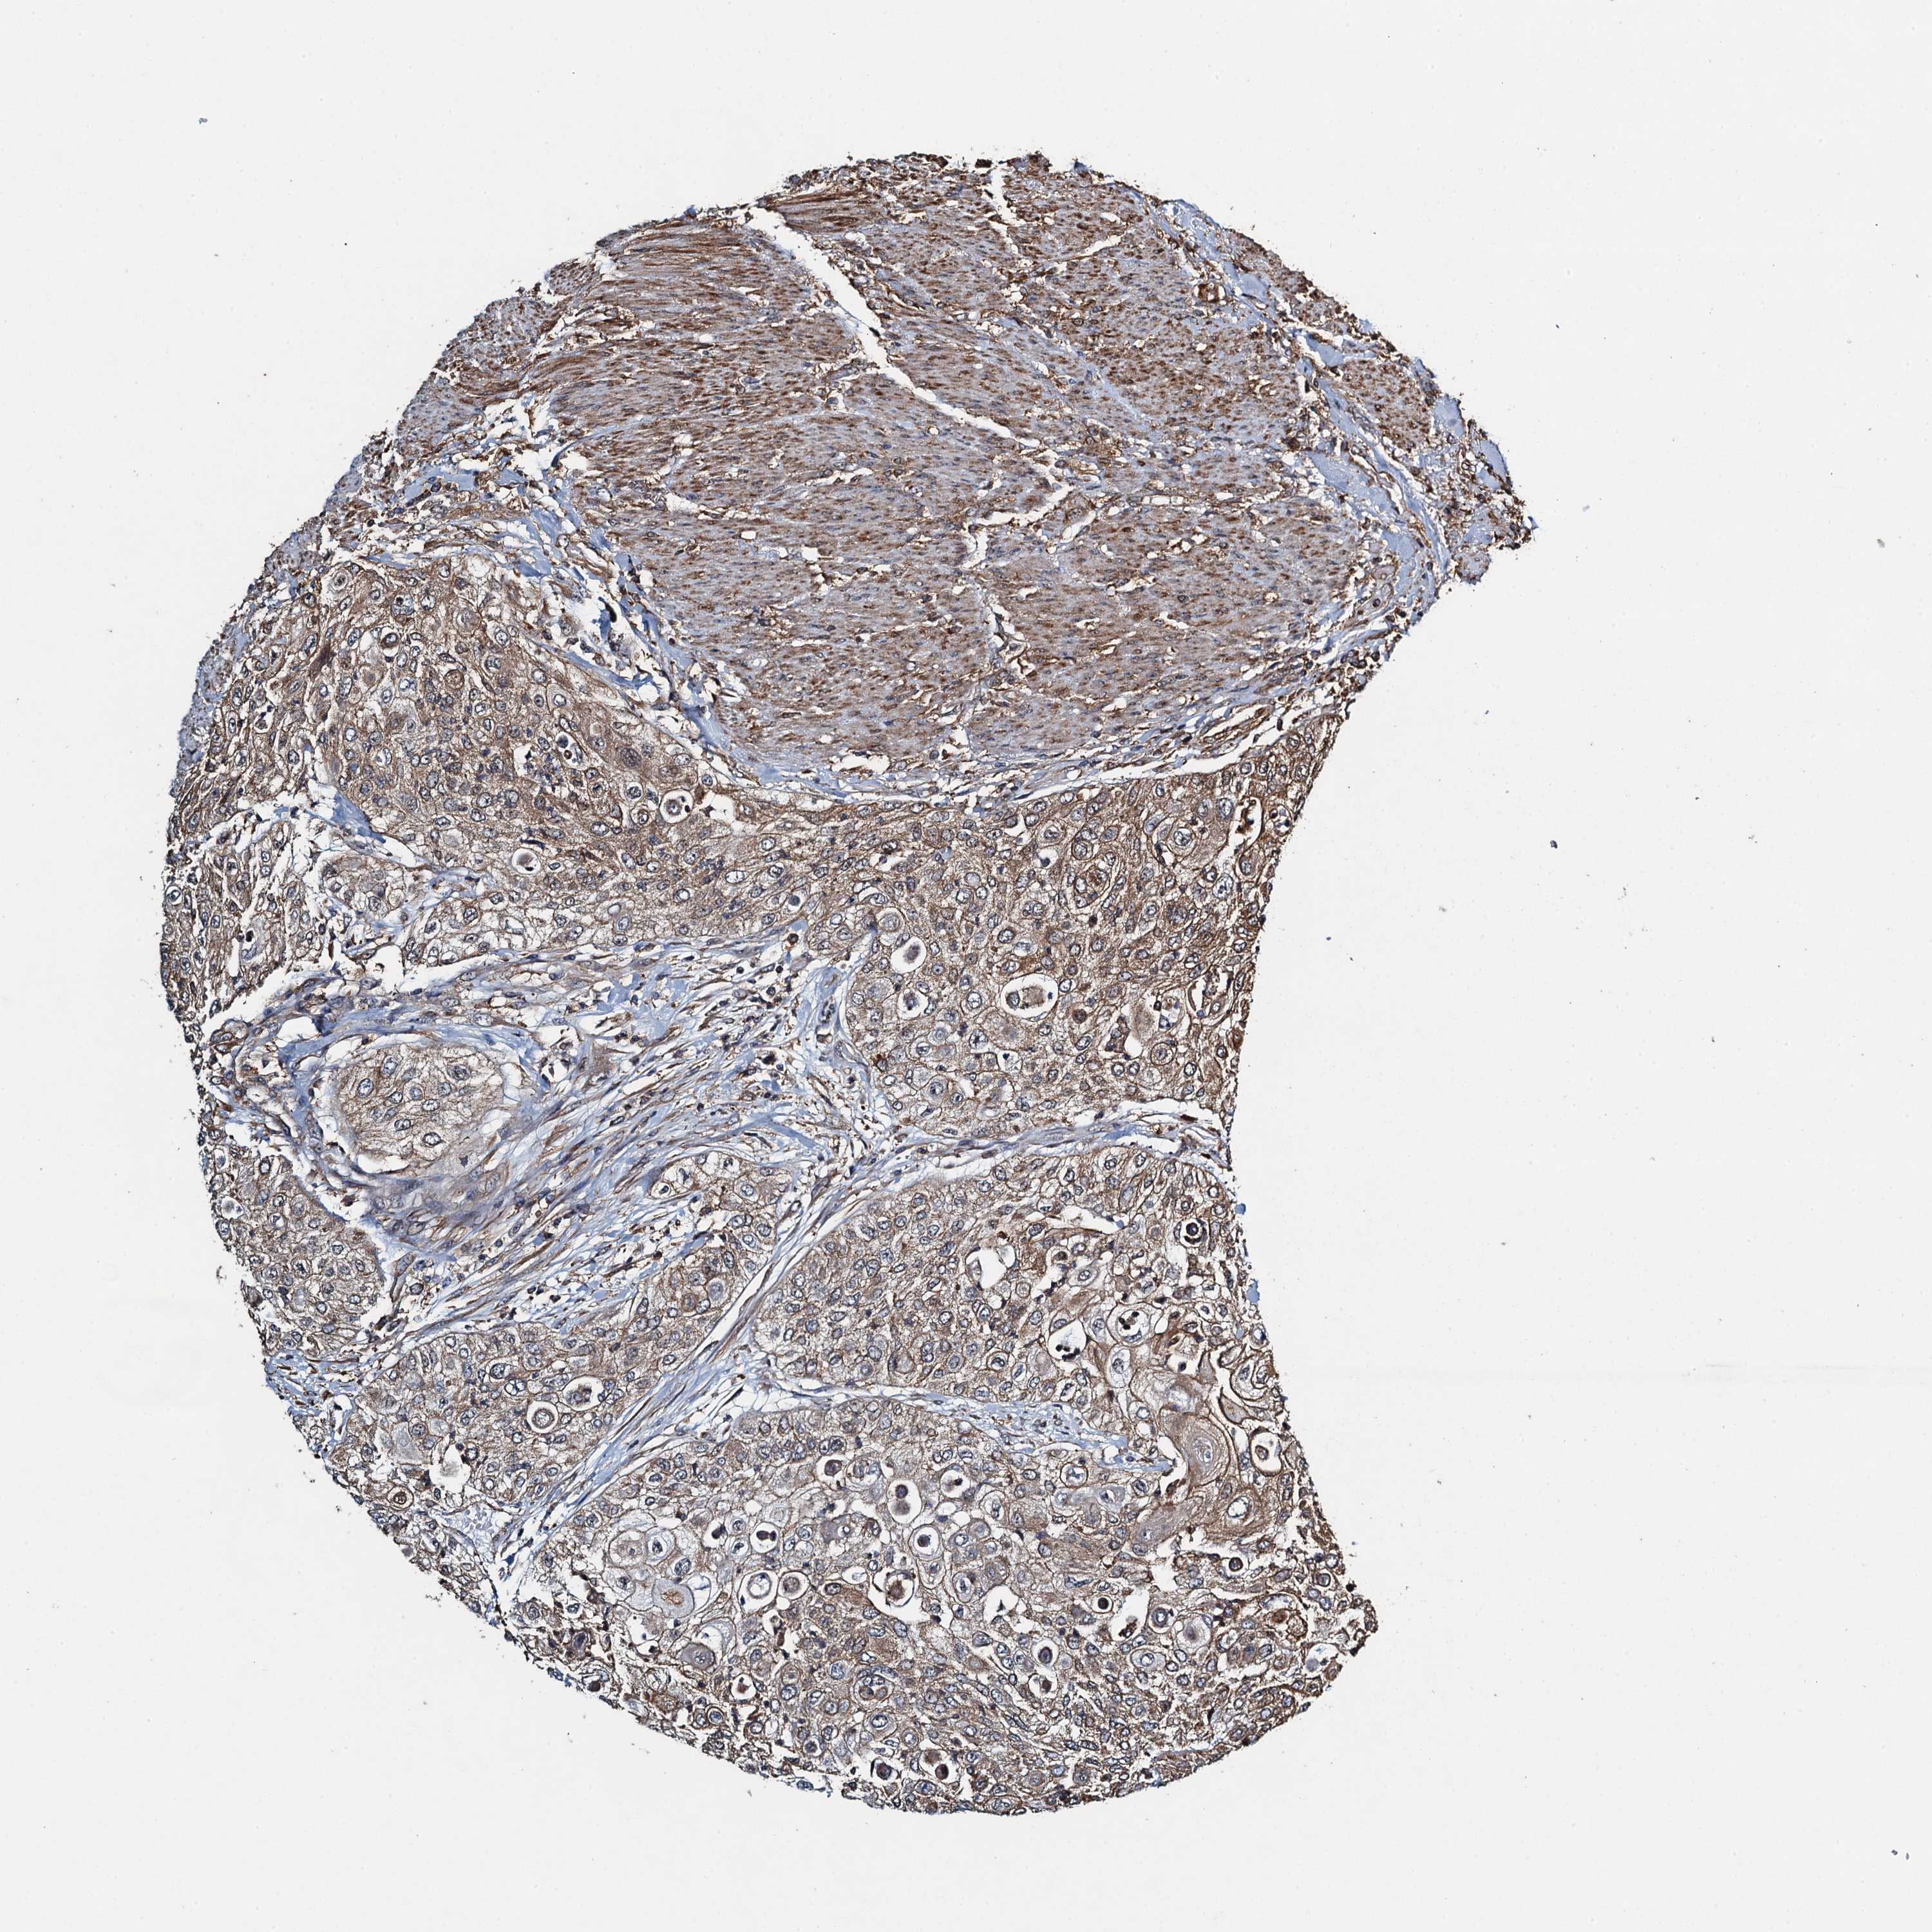

UROTHELIAL CANCER - Protein expressioni

A mouse-over function shows sample information and annotation data. Click on an image to view it in a full screen mode. Samples can be filtered based on level of antibody staining by selecting one or several of the following categories: high, medium, low and not detected. The assay and annotation is described here.

Note that samples used for immunohistochemistry by the Human Protein Atlas do not correspond to samples in the TCGA dataset.

Antibody stainingi

Antibody staining in the annotated cell types in the current human tissue is reported as not detected, low, medium, or high, based on conventional immunohistochemistry profiling in selected tissues. This score is based on the combination of the staining intensity and fraction of stained cells.

Each image is clickable and will lead to virtual microscopy that enables deeper exploration of all samples and also displays staining intensity scores, fraction scores and subcellular localization as well as patient and tissue information for each sample.

Antibody HPA039690

Antibody HPA040231

Urothelial carcinoma, High grade

Urothelial carcinoma, Low grade